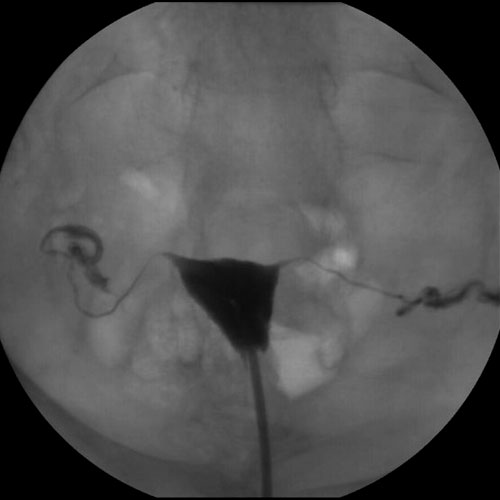

This is an example of an xray that was in my chart… again, this is not my actual xray…

Apparently, fallopian tubes look like a frog to Punky.